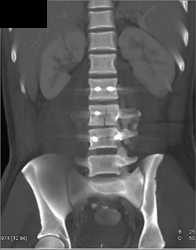

Tibial Fracture